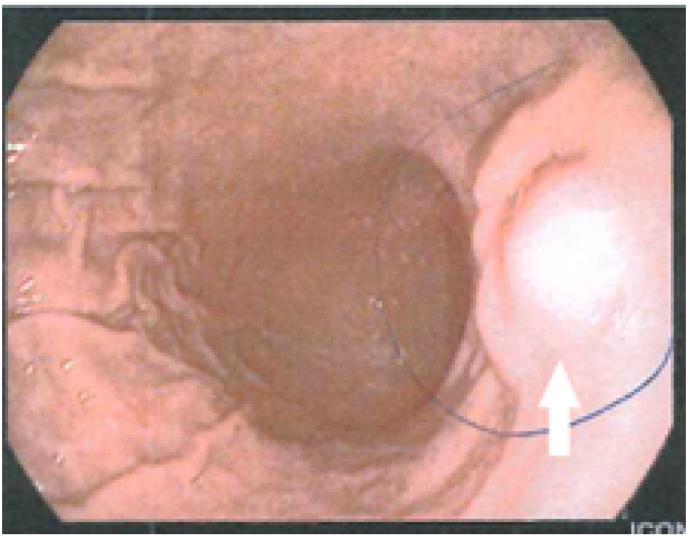

In our case a 52-year-old woman, with heartburn as the only symptom, was undergone successive examinations, indicating a subepithelial lesion in the antrum of the stomach, from which only Magnetic Resonance Imaging (MRI) indicated the presence of ectopic pancreas, while Computed Tomography results considered the mass as Gastrointestinal Stromal Tumor. Wedge gastrectomy was performed in order to extract the lesion and the histopathological examination confirmed the findings of the MRI. The patient fully recovered with no complications.

In most cases, EP is described in endoscopy as a subepithelial mass with normal mucosa. As EP can mimic other subepithelial masses, even adenocarcinoma, it is of utmost importance not to omit the performance of surgical removal and histopathological examination. Consequently, resection is essential not only for the diagnosis but also for the treatment of the patient.

在我们的病例中,一名52岁女性,唯一症状为烧心,接受了一系列检查,显示胃窦有上皮下病变,其中只有磁共振成像(MRI)提示存在异位胰腺,而计算机断层扫描结果认为该肿块是胃肠道间质瘤。为切除病变进行了楔形胃切除术,组织病理学检查证实了MRI的结果。患者完全康复,无并发症。

在大多数情况下,内镜检查将EP描述为具有正常黏膜的上皮下肿块。由于EP可模仿其他上皮下肿块,甚至腺癌,因此绝不遗漏手术切除和组织病理学检查至关重要。因此,切除不仅对诊断至关重要,对患者的治疗也至关重要。